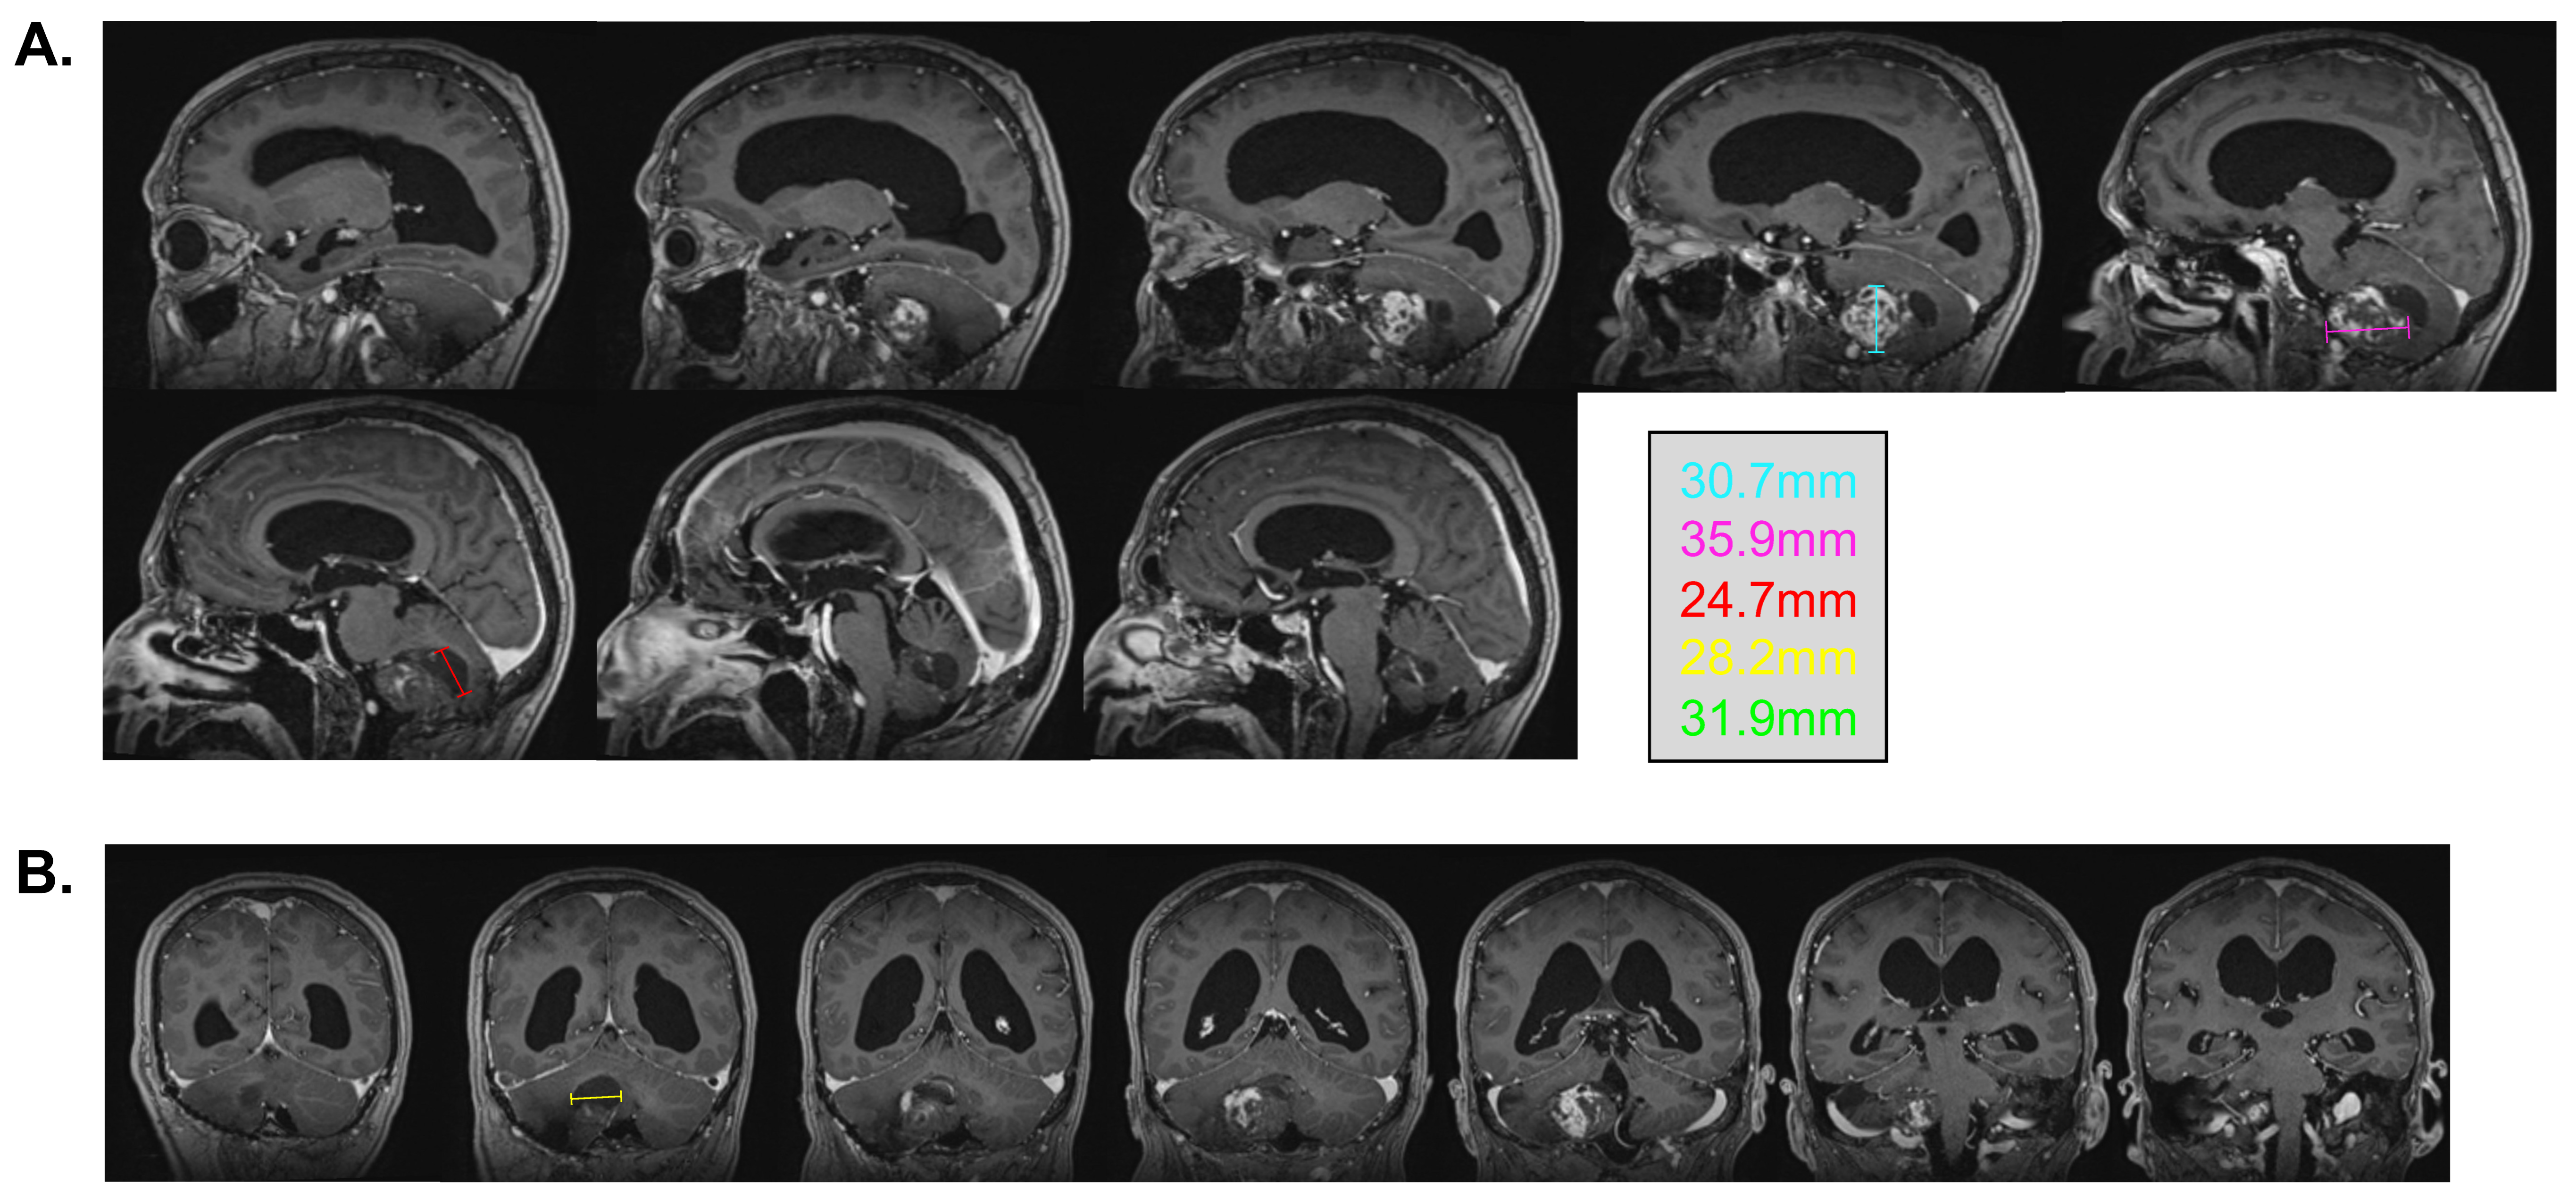

In February 2022, at the age of 72 years old, the patient was hospitalized in his hometown following the appearance of symptoms and was referred to neurosurgery. He mainly displayed loss of balance, unexplained loss of weight, confusion, and psychomotor retardation. He was able to ambulate without the aid of a walker, albeit at a very slow pace. Dexamethasone failed to improve his condition. An MRI underlined a right-sided, cerebellar intra-axial lesion located at the anterolateral portion of the cerebellar hemisphere. The lesion, determined to be a relapse of the initial HBL, displayed a nodular component in intimate proximity with the brainstem, measuring 36.2 × 32.1 × 31.9 mm (Figure 3). The presence of two cystic components were also noted. The first, located posteriorly, measured 32 mm maximally (Figure 4, blue marker). The second, located antero-infero-medially, measured 21 mm maximally and protruded in the subarachnoid space at the level of the pons (Figure 4, pink marker). The lesions caused a mass effect on the medulla, the inferior aspect of the pons, the middle cerebellar peduncle, and at the level of the 4th ventricle with associated hydrocephalus.

Figure 3.

Pre-surgical MRI of the lesion. Representative capture of the T1-weighted MRI pre-surgical imaging. Representative measurements are color-coded. (A) Sagittal images are organized left to right and represent a left–right progression in the sagittal plane. (B) Coronal images are organized left to right and represent a posterior-to-anterior progression in the coronal plane.